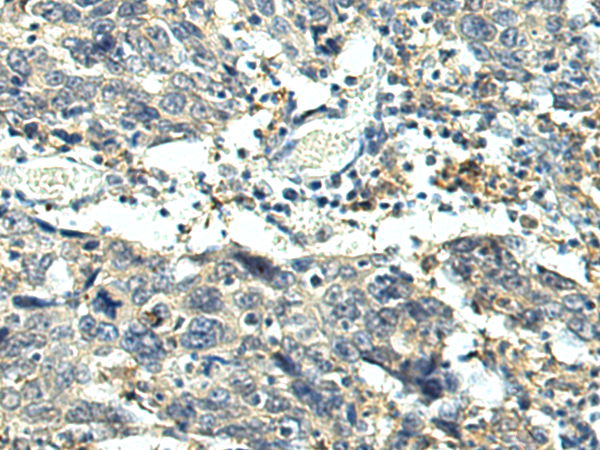

IHC positive control: |

Human esophagus cancer and Human gastric cancer |

IHC Recommend dilution: |

100-500 |